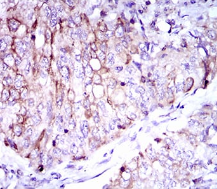

CD7 Mouse Monoclonal antibody[4D4F8]

IHC    1/200 - 1/1000